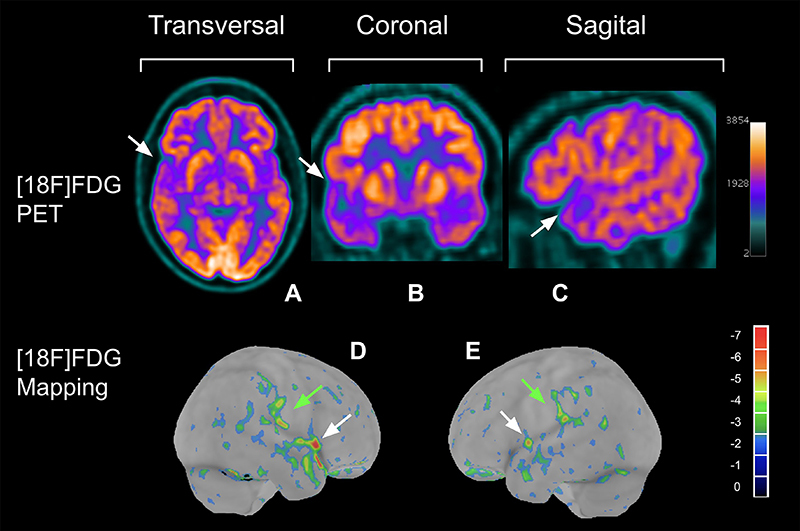

由 SARS-CoV-2 引起的 COVID-19 表现出多种症状,包括神经系统表现。本研究调查了 COVID-19 的神经系统后遗症,重点是通过 PET/CT 评估脑糖酵解代谢对中枢神经系统的影响。22 名有轻度长 COVID 认知症状的患者和 20 名无认知、精神或神经损伤且无 COVID-19 感染史的健康志愿者接受了脑 PET/CT 扫描,使用 [18F]FDG 评估脑代谢。研究采用 CortexID Suite 软件进行定量分析,细致评估了不同脑区对 [18F]FDG 的摄取情况。分析的重点是确定代谢低下和代谢亢进的区域,这表明葡萄糖代谢的改变可能与 COVID-19 对神经系统的影响有关。轻度 COVID 组和健康组之间没有发现明显的统计学差异。虽然我们的样本太少,无法得出组间的统计学差异,但未来的研究应探讨一些发现,如轻度 COVID 组中 15 个区域代谢低下,11 个区域代谢亢进。这些变化,尤其是与执行功能、感官知觉和情绪调节有关的区域的变化,表明大脑功能发生了细微的改变。我们的研究没有发现轻度长程COVID患者体内有明显的糖代谢变化。然而,在一些患者身上发现的糖代谢不足和糖代谢亢进区域与他们表现出的认知和情感症状具有生物学上的合理性。今后的研究应将更多样本与神经心理学和神经精神病学检查联系起来,以证实这种关系。

COVID-19, caused by SARS-CoV-2, presents diverse symptoms, including neurological manifestations. This study investigated COVID-19's neurological sequelae, focusing on the central nervous system's involvement through cerebral glycolytic metabolism assessed via PET/CT. Twenty-two patients with mild long COVID cognitive symptoms and 20 healthy volunteers without cognitive, psychiatric, or neurological impairments and no history of COVID-19 infection underwent cerebral PET/CT scans using [18F]FDG to assess cerebral metabolism. The study meticulously evaluated the uptake of [18F]FDG in various brain regions, employing the CortexID Suite software for quantitative analysis. The analysis focused on identifying areas of hypometabolism and hypermetabolism, indicative of altered glucose metabolism possibly related to COVID-19's neurological impact. No statistically significant differences were found between the mild COVID and healthy groups. Although our sample was too small to generate a statistical difference between groups, future studies should explore some findings, such as hypometabolism in 15 regions and hypermetabolism in 11 regions in the mild COVID group. These changes, especially in areas linked to executive functions, sensory perception, and emotional regulation, suggest nuanced alterations in brain function. Our study did not find significant glycolytic metabolic changes in patients with mild long COVID. However, areas of glycolytic hypometabolism and hypermetabolism found in some patients showed biological plausibility with the cognitive and affective symptoms they presented. Future investigations with a larger sample size should be correlated with neuropsychological and neuropsychiatric examinations to confirm this relationship.